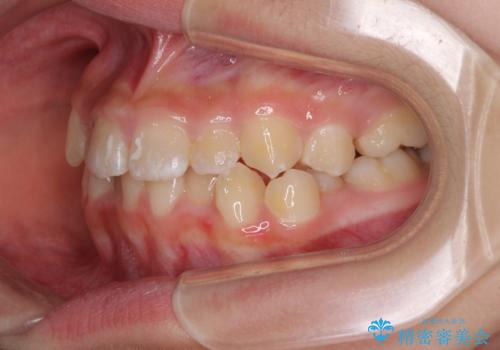

遠方から新幹線で通院 急速拡大装置とインビザラインによる矯正治療

- 小児矯正の頃から診察を行っている患者様です。

上顎骨の幅が下顎骨よりも小さいので、拡大装置により骨幅を広げて上下関係を改善し、その後インビザラインにて歯並びを整えることとしました。

上下の骨幅を改善したことで、スムーズに歯列矯正を行うことができました。

インビザライン治療開始直後に遠方に引っ越しをされたため、通院間隔が長くなり、治療期間が長くなりましたが、しっかりと治療を行うことができました。